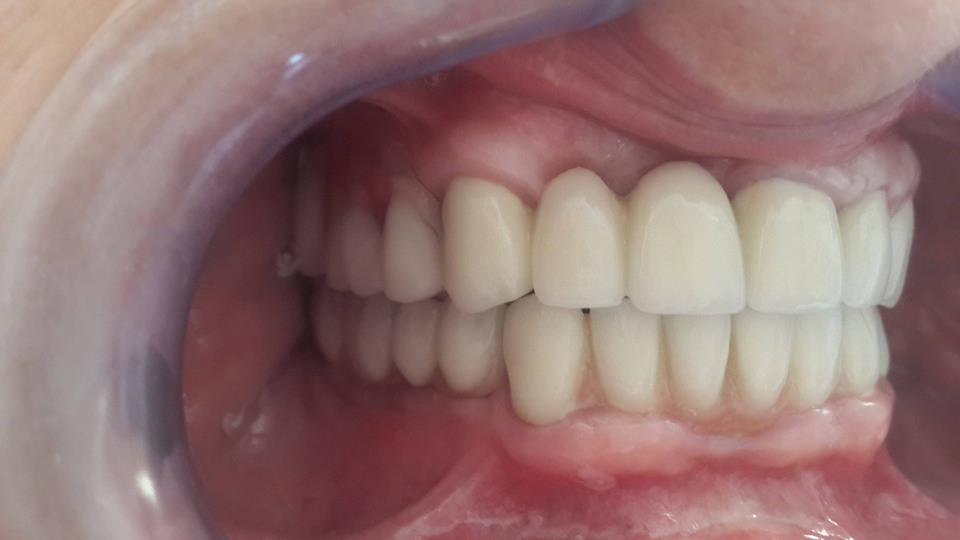

An example of complete rehabilitation of the oral cavity. Treatment included the removal of the old prosthesis, treatment of paradontitis, removal of a large cyst, implantation, clasp prosthesis.